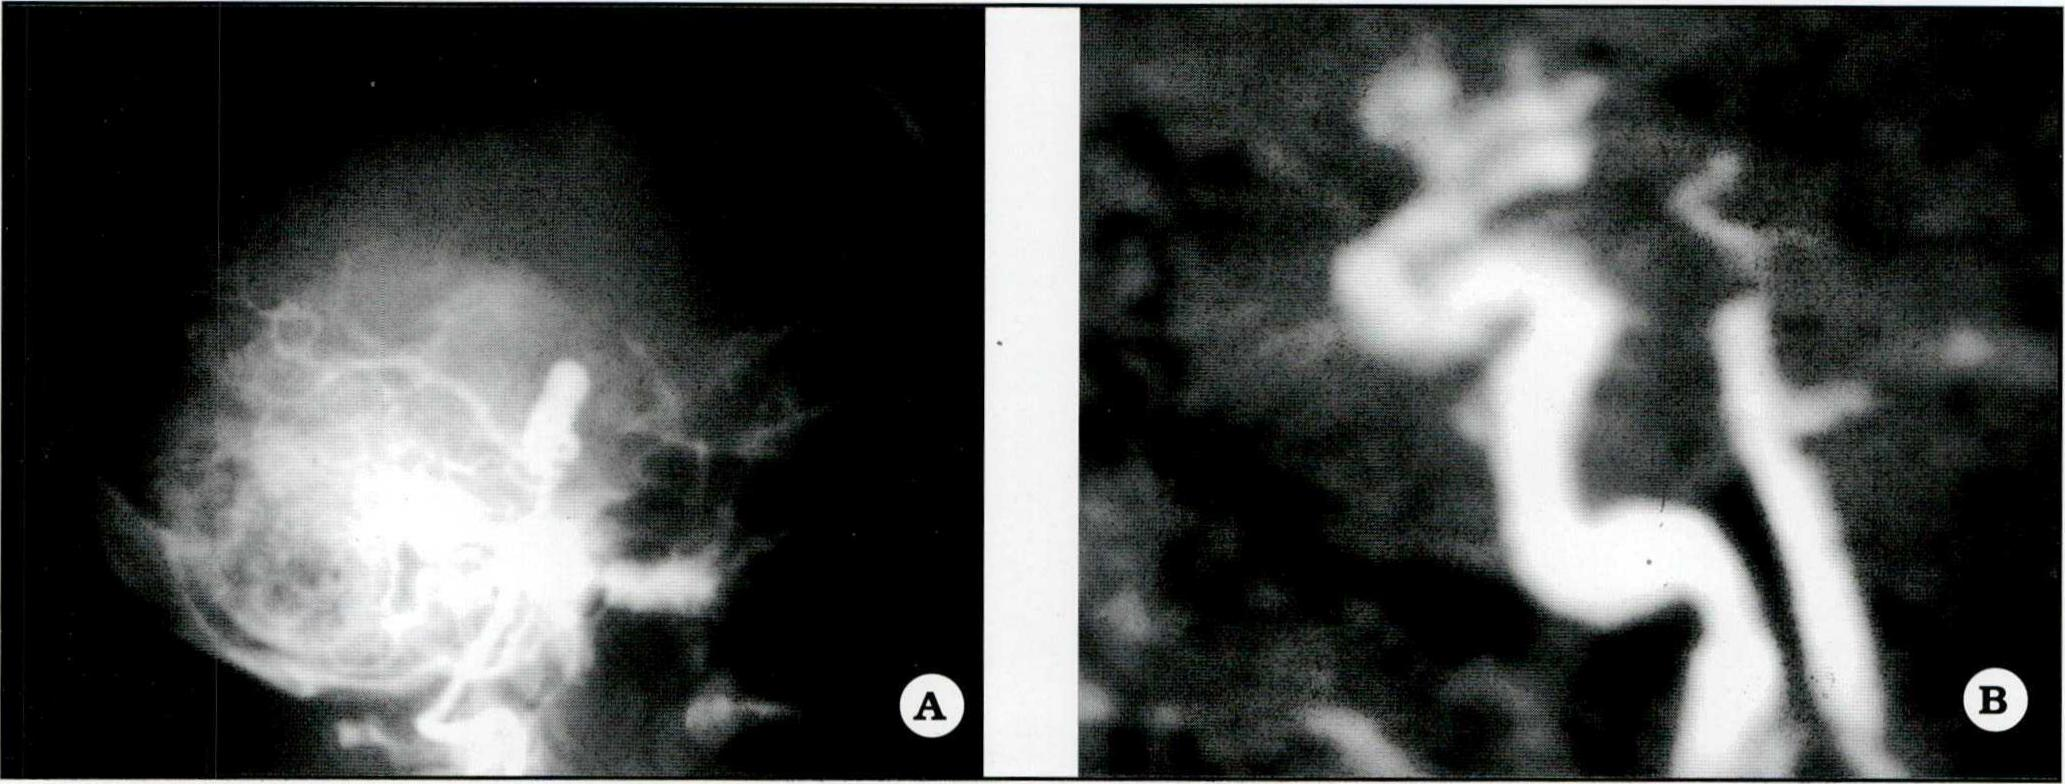

- Aneurisma del ápex de la arteria basilar (Fig. 4).

Fig 4. A. Angiograma preoperatorio de un aneurisma del apex de la arteria basilar (proyección perfil). B. Angiorresonancia de control postoperatorio correspondiente al aneurisma basilar, con exclusión del mismo por clipado.